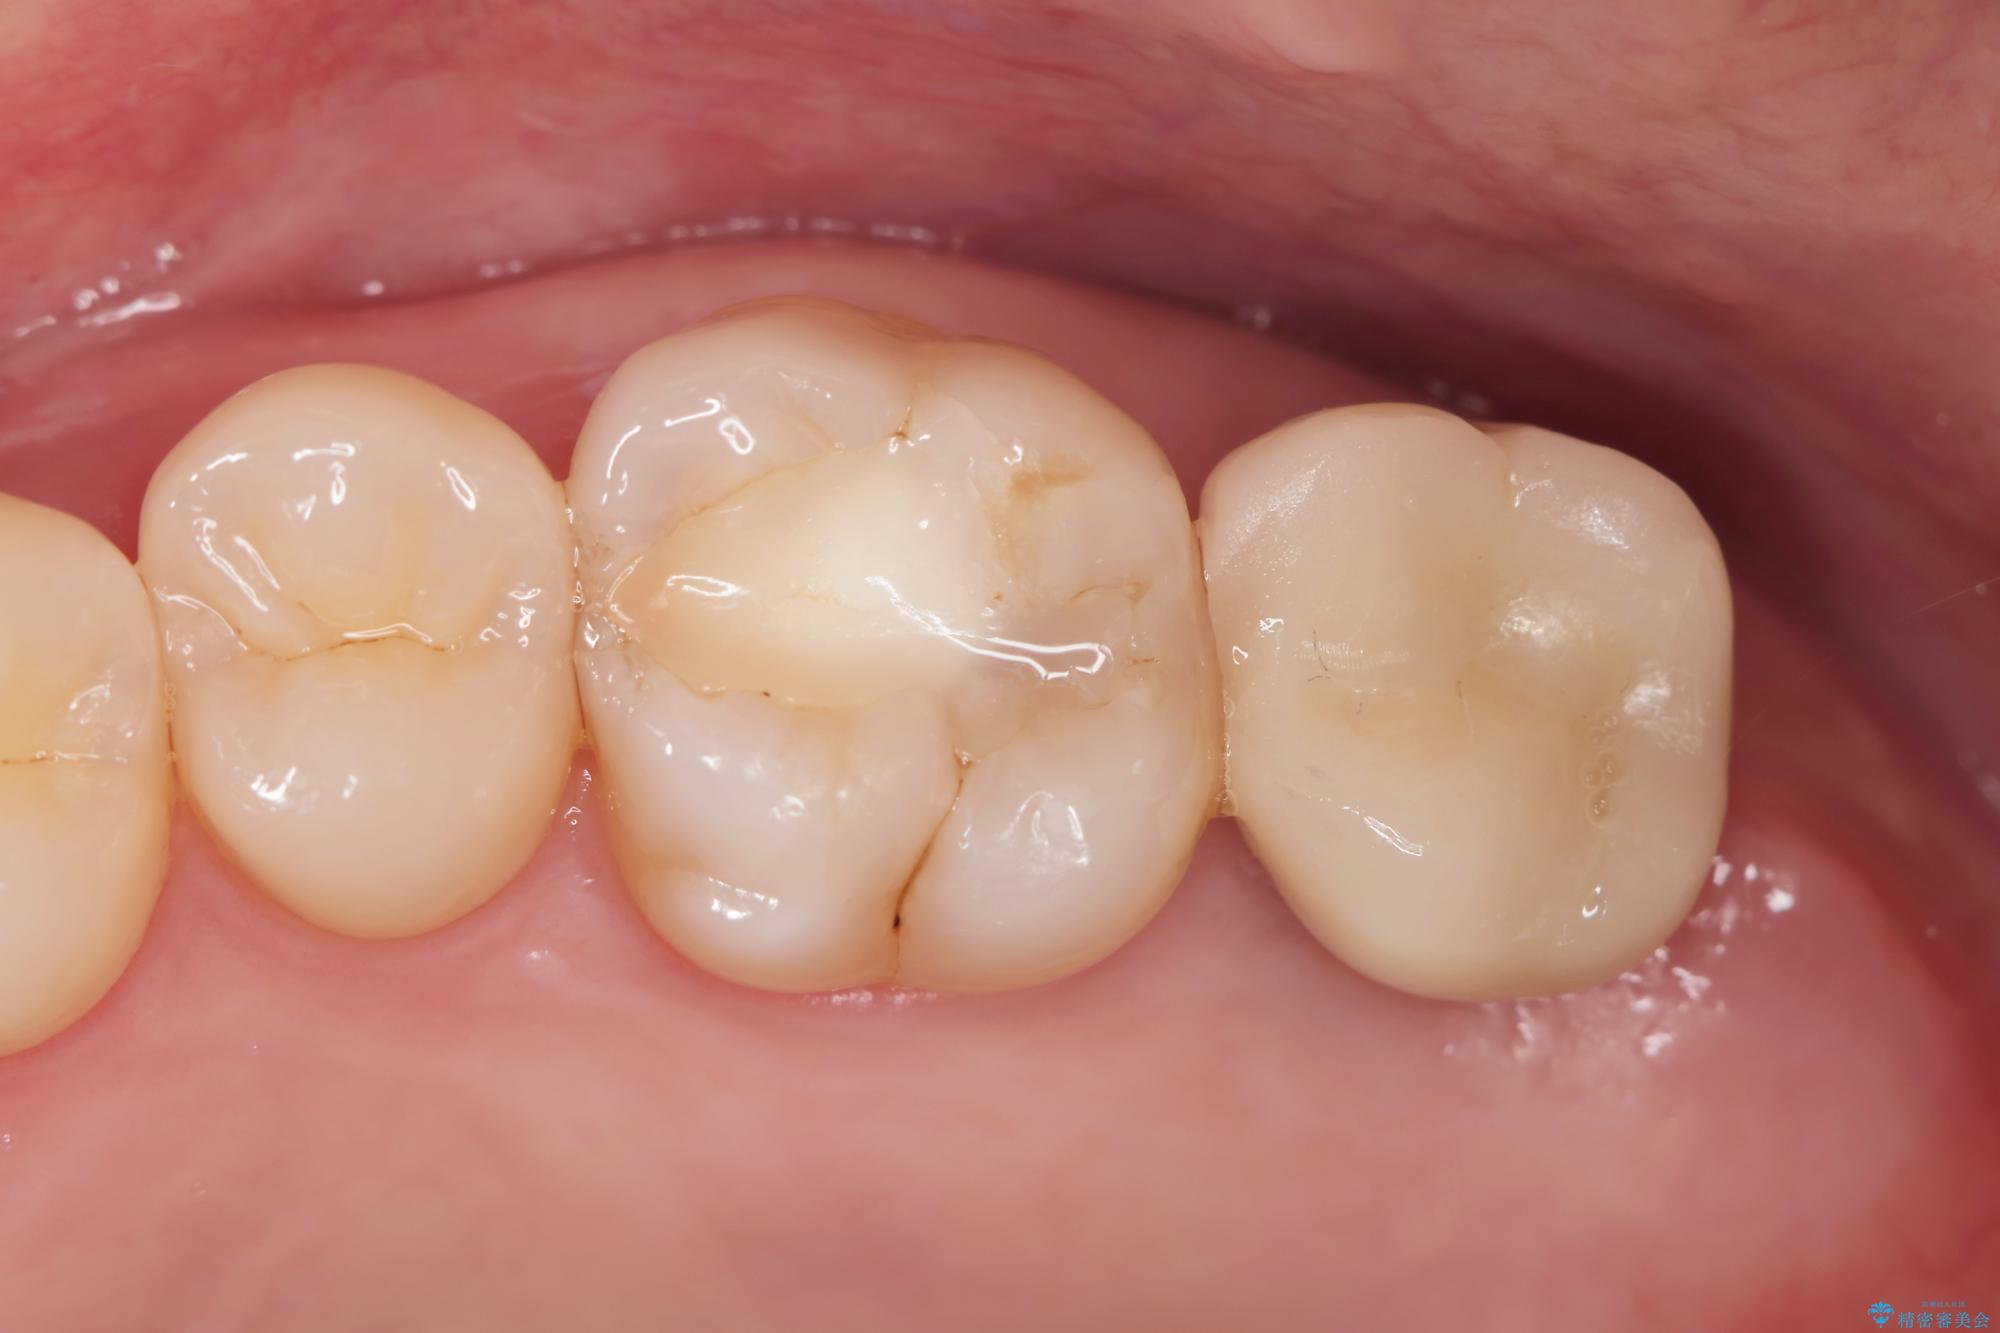

治療前

【噛むと歯が疼く】歯牙破折からのインプラント治療 治療前画像 【噛むと歯が疼く】歯牙破折からのインプラント治療 治療前画像 【噛むと歯が疼く】歯牙破折からのインプラント治療 治療前画像 【噛むと歯が疼く】歯牙破折からのインプラント治療 治療前画像 【噛むと歯が疼く】歯牙破折からのインプラント治療 治療前画像 【噛むと歯が疼く】歯牙破折からのインプラント治療 治療前画像 【噛むと歯が疼く】歯牙破折からのインプラント治療 治療前画像